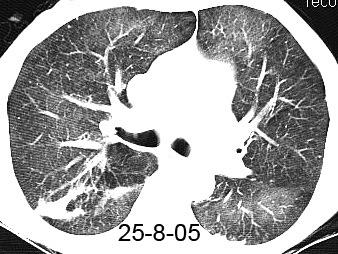

14-4-03

Atelectasia del LSI por Ca. de pulmón.